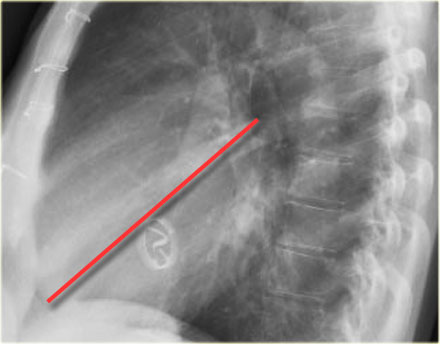

Spine Sign

When evaluating the vertebral bodies on the lateral view, they should appear progressively more radiolucent (darker) from top to bottom due to the increasing amount of aerated lung overlying them (white arrow).

If the lower thoracic vertebrae appear abnormally dense, it may indicate pathology in the lower lobes, such as consolidation or mass lesions — this is known as the spine sign.

Diaphragm Evaluation

• The right hemidiaphragm should be clearly visible anteriorly up to the chest wall (red arrow), representing the interface between aerated lung and abdominal soft tissues.